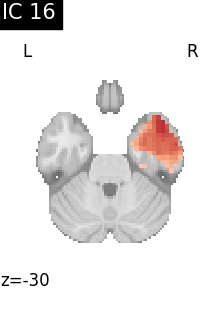

Finally, we plot the map for each ICA component separately

from nilearn.image import iter_img

from nilearn.plotting import plot_stat_map, show

for i, cur_img in enumerate(iter_img(canica_components_img)):

plot_stat_map(

cur_img,

display_mode="z",

title=f"IC {int(i)}",

cut_coords=1,

vmax=0.05,

vmin=-0.05,

colorbar=False,

)

show()